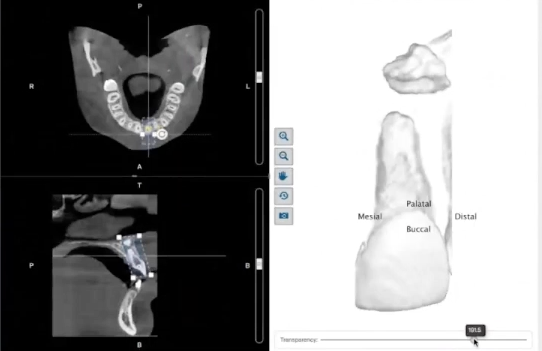

In this presentation you will learn the entire digital workflow to plan and place an implant accurately.In this unique lecture you will go through the entire workflow including Intraoral Scanning, CBCT, Implant Planning, Implant Guide Design, 3D Printing, and Guided Implant Placement.